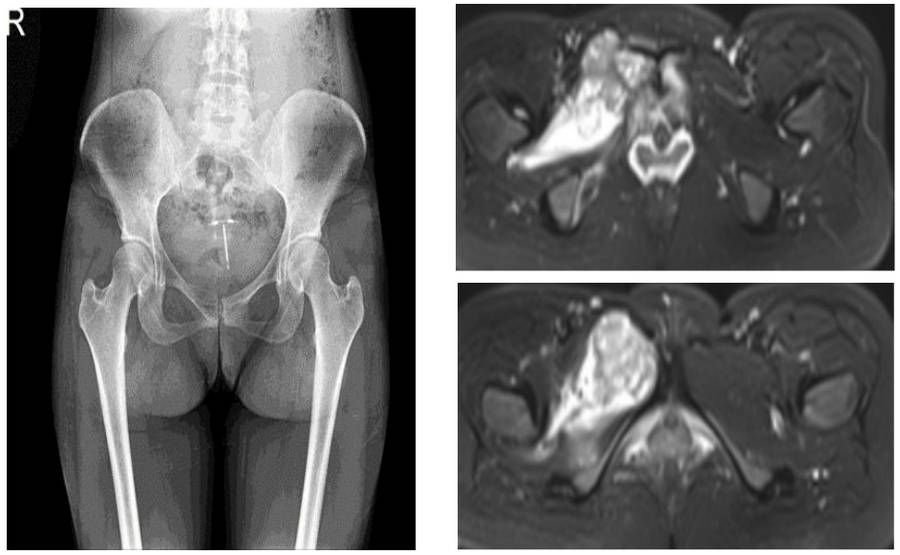

Ameliyat Öncesi: Röntgende sağ pubik kolda düzensizlik, MR’da eşlik eden yumuşak doku komponenti ve peritümöral ödem görülmekte